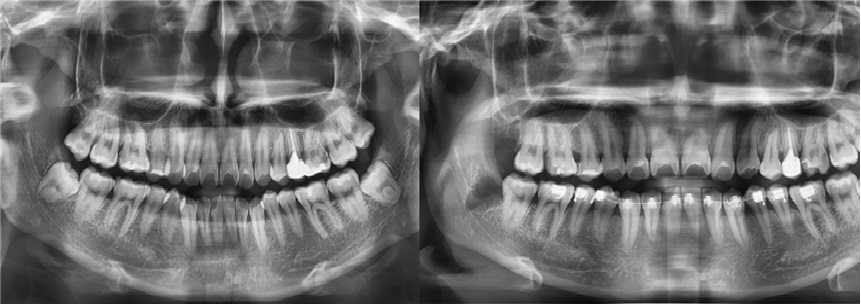

치료전후사진